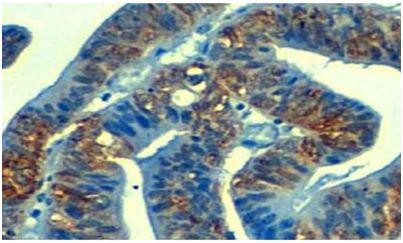

在一项新的研究中,来自西班牙Bellvitge生物医学研究所(Bellvitge Biomedical Research Institute, IDIBELL)表观遗传学与癌症生物学项目主任Manel Esteller和他的团队发现癌症化疗中一种产生多重耐药性的原因。相关...